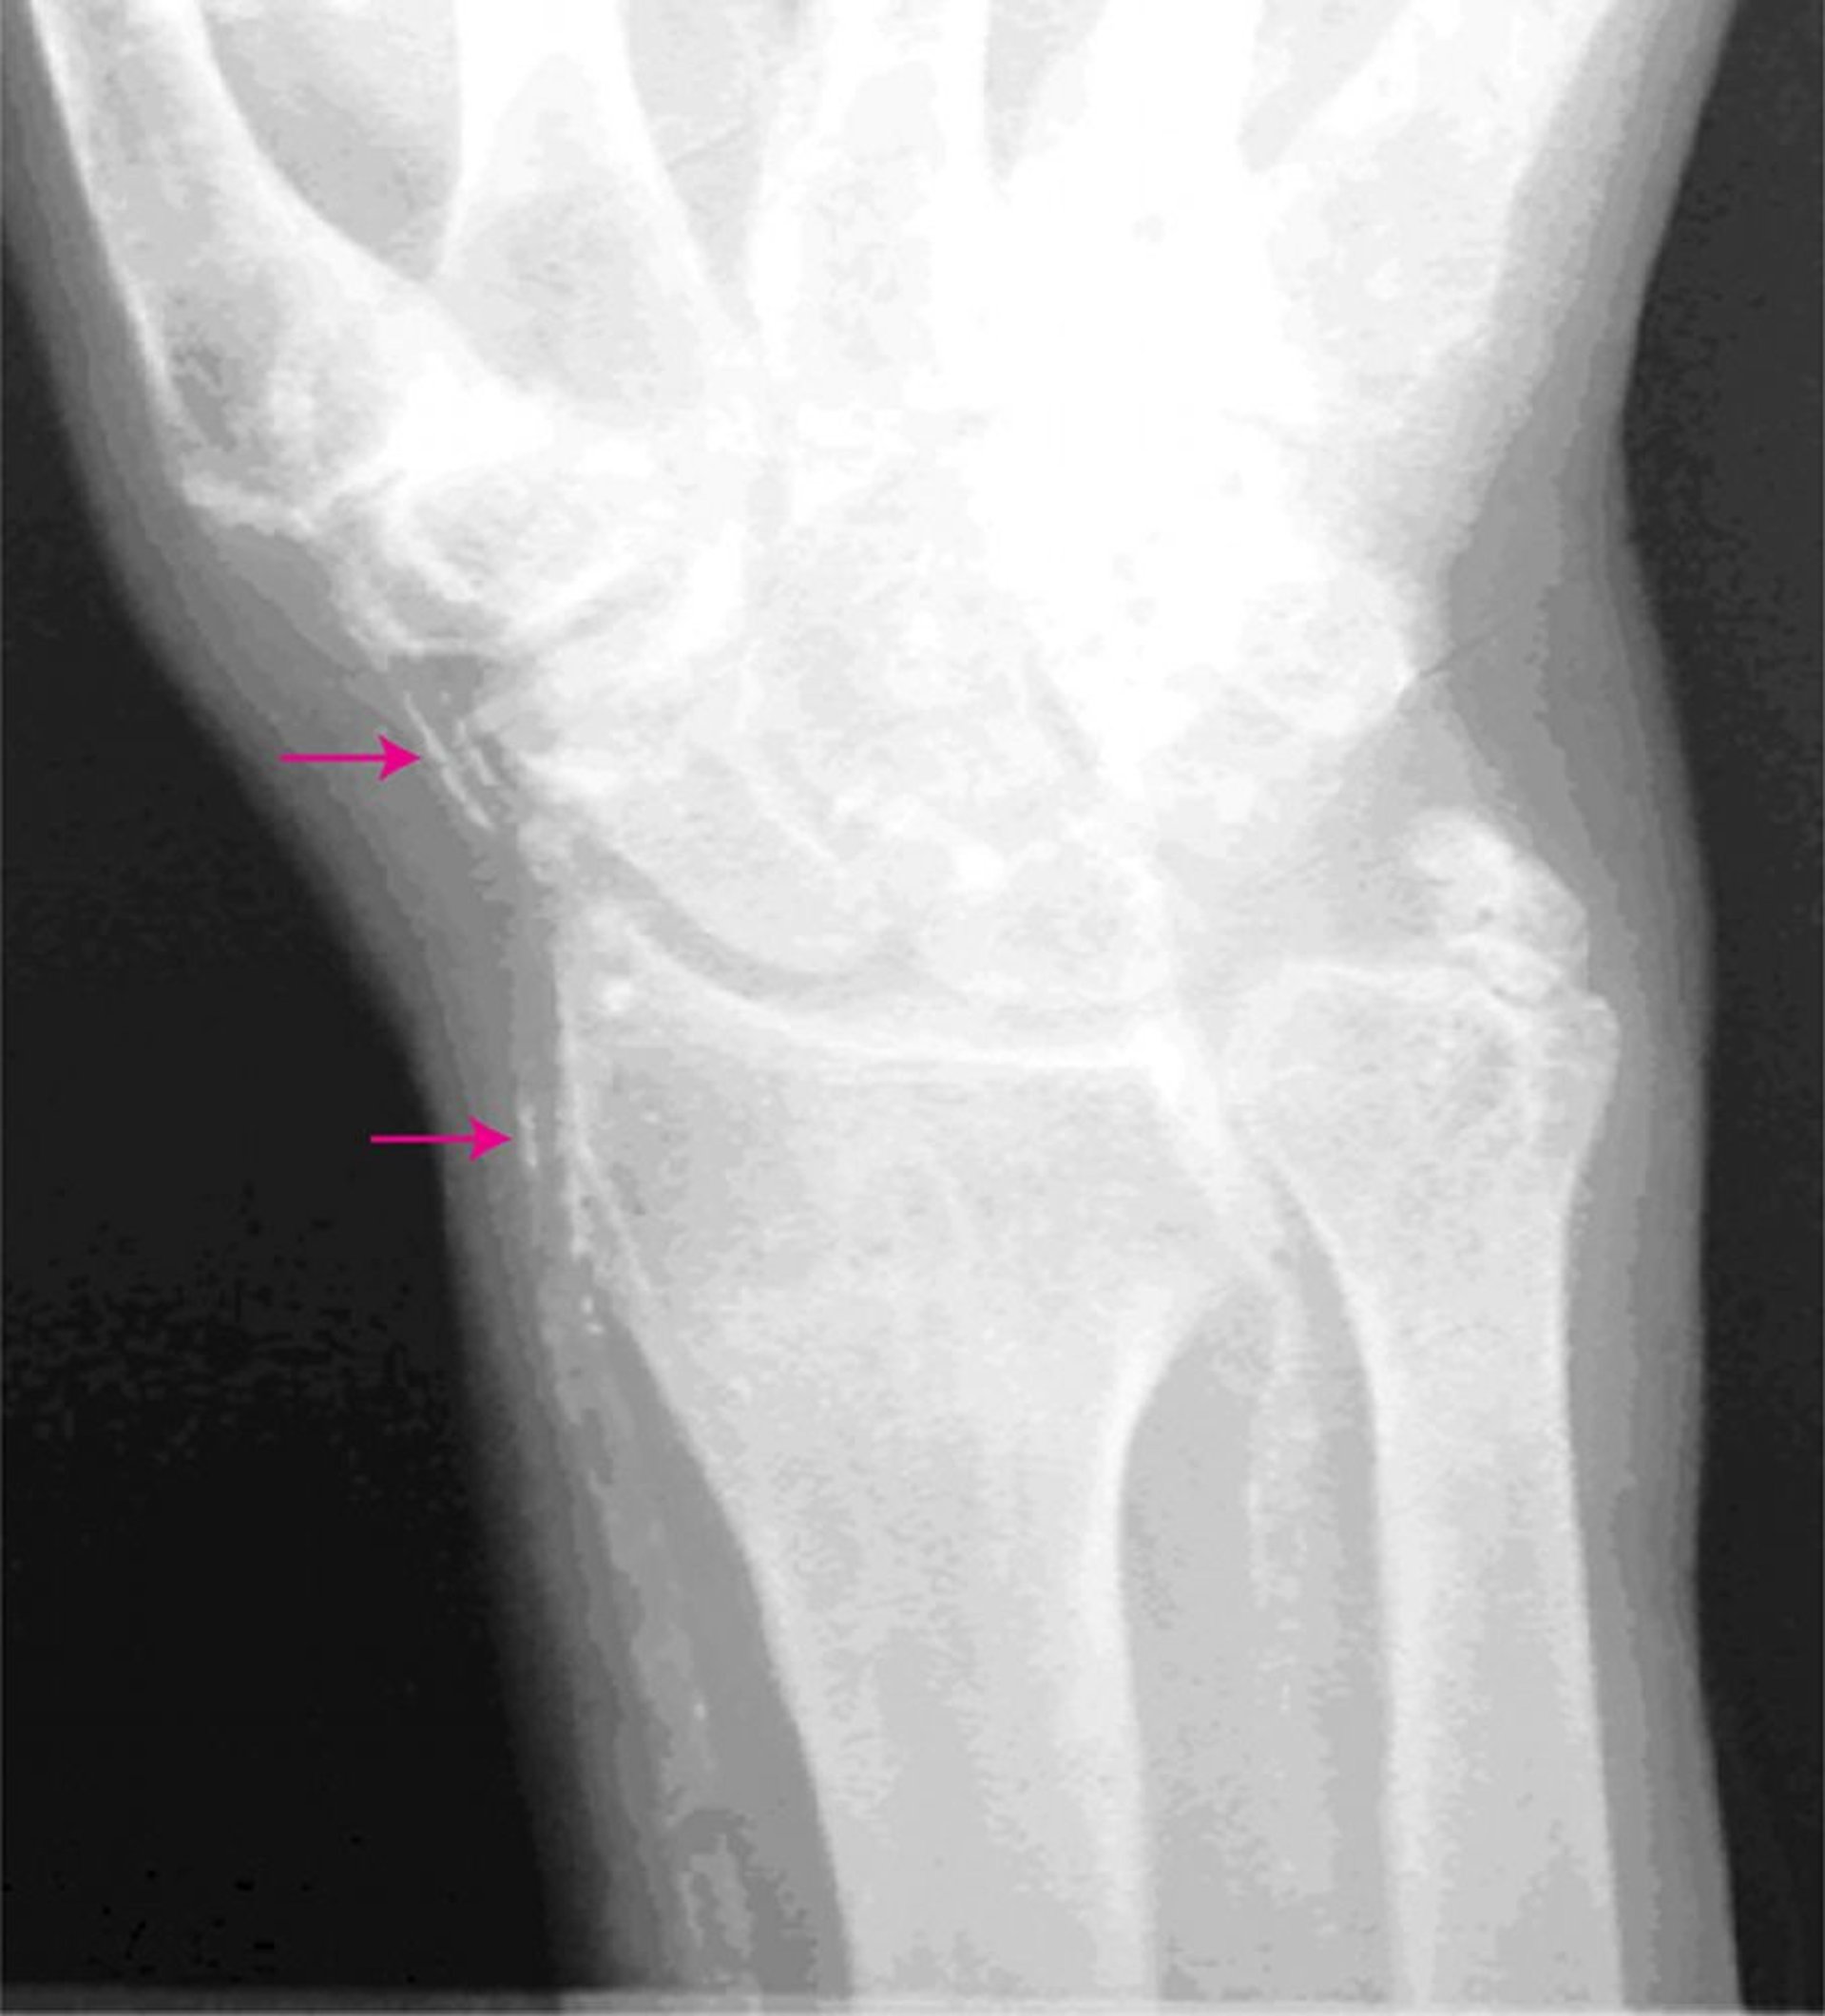

Атеросклероз Менкеберга

Этот рентгеновский снимок руки показывает кальцинированные артерии (стрелки).